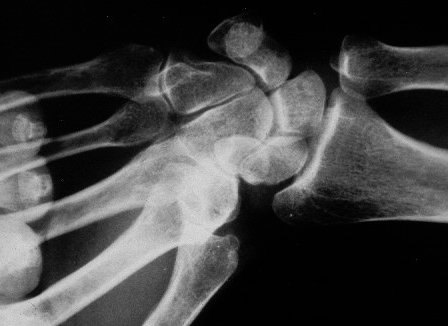

Kinematic wrist clenched fist radial deviation Xray view

Xray beam angle: 90 degrees.